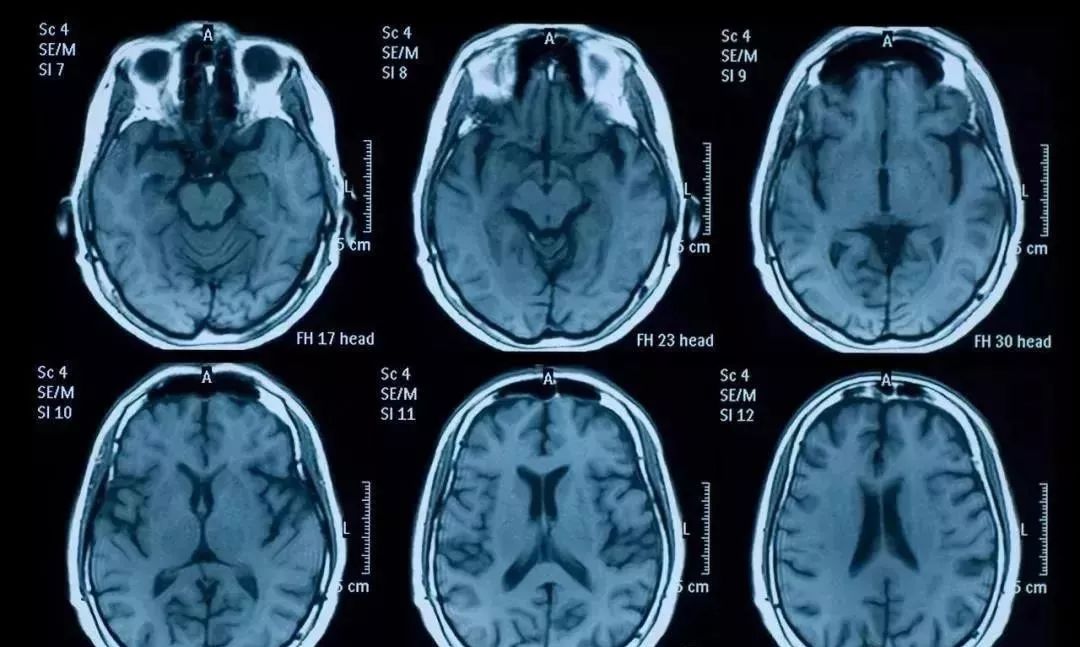

神经系统-阿尔兹海默症

阿尔兹海默症(老年痴呆症)是一种多因素引起、病理机制复杂的神经系统退行性病变,也是一种较为常见老年性疾病,直接影响老年人的认知功能。虽然现在药物可以在早期延缓疾病发展的作用,但是却没有办法进一步遏制阿尔兹海默症的进一步恶化。

人在进入中年后,脑神经细胞逐渐减少,25岁以后年减少约0.8%,到了70岁时脑神经只剩下55%。老年人往往由于神经细胞数量减少,脑神经功能减退,表现为记忆力变差、认知力减退、智力衰退、失眠和老年痴呆等。

干细胞能分化形成新的神经细胞,为大脑提供了全新细胞,可有效的改善脑衰老状况。老年性痴呆患者的记忆力和智力有明显的提高和恢复且疗效持久、稳定。这意味着,干细胞疗法能有效减缓或阻止阿尔茨海默病的发展, 甚至逆转阿尔茨海默病所造成的损害。